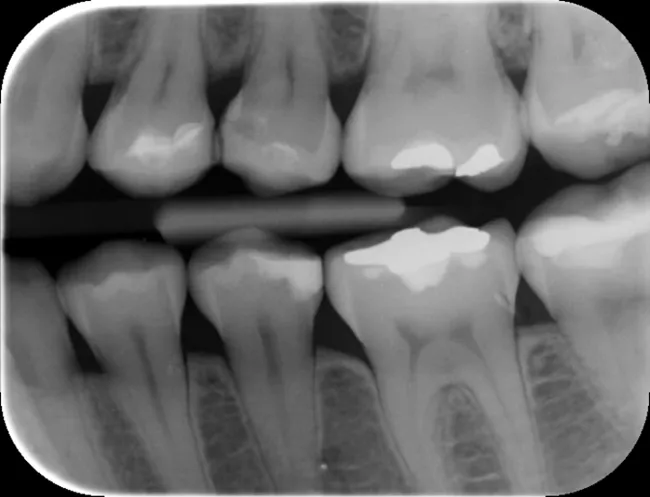

Między zębami: niewidoczny wróg, którego zdradza nić dentystyczna i RTG

Próchnica rozwijająca się między zębami jest szczególnie podstępna, ponieważ jest praktycznie niewidoczna gołym okiem. Pierwszym sygnałem, który może ją zdradzić, jest strzępienie się nici dentystycznej podczas czyszczenia przestrzeni międzyzębowych. Stomatolog jest w stanie wykryć ten rodzaj próchnicy za pomocą zdjęć rentgenowskich, gdzie widoczny jest ciemny cień prześwitujący przez szkliwo na powierzchniach stycznych zębów.